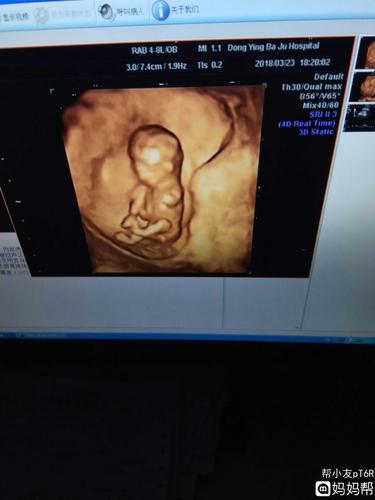

nt过啦,给你们欣赏一下照片吧!能看出男

nt单可看男女准确率90nt可以看男女吗

怀男孩nt图片

已生男孩nt图片